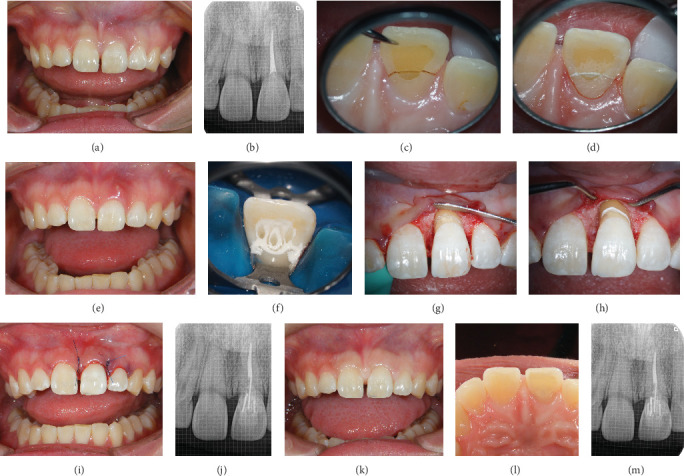

Objective: The aim of this study is to present cases of root preservations in which minor surgery and characteristic multifiber foundation were performed to treat maxillary central incisor root fractures near the bone margin. Clinical Considerations: Two patients experienced root fractures of the central incisors due to short- or long-term trauma. Orthodontic extrusion was not employed in both cases; instead, minimal periodontal surgery was performed as pretreatment. In cases where the patient's tooth remained intact, fractured pieces were bonded. However, in cases where the root of the tooth was fractured with the prosthesis, a new restoration was fabricated. The roots were constructed using multiple characteristically placed glass fiber posts and materials with high biocompatibility and hydrophilicity as the foundation. Fractured teeth were esthetically restored using conservative or prosthetic treatment methods, resulting in patient satisfaction. No complications were observed at the 4-year follow-up. Conclusions: Although horizontal root fractures near the alveolar bone are generally considered to have a poor prognosis and esthetic outcome, they can be restored esthetically with minimal invasion by selecting appropriate procedures and materials.

Abstract Image